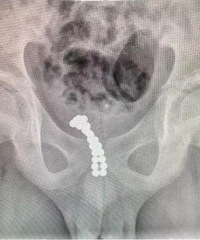

第一次详细地描述从备孕至今的经历,希望给一些相同经历朋友提供参照!我和我老公是大学同学,2016年10月2日结婚了。我们一直以顺其自然的心态去迎接新生命,但是,结婚半年一直没怀上,周围的亲戚朋友开始催我们要孩子!我是扛不住压力的人,因此在我姑姑的强迫下开始进行问诊! 我认真按照医生的要求定时定点进行监控及调理,因为月经不规律及孕酮较低的情况

查看详情>>